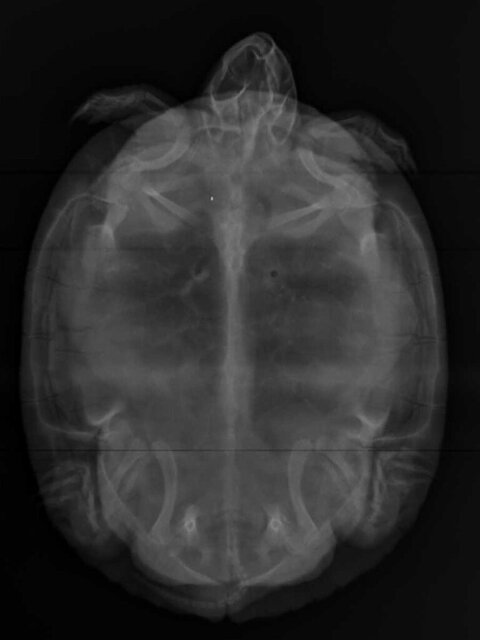

Алексей Alex-Raduga Ваше имя: Алексей Локация: Россия, МО, Серпуховский район Опубликовано: 18 сентября 2023 Автор Опубликовано: 18 сентября 2023 @moth Здравствуйте ! Возил в Серпухов к Савиной, сделали рентген, она сказала есть 5 яиц и все с ними нормально, пока наблюдать, назначила кальций - кальция глюконат 100мг/мл - 0,3мл 1 раз в день 7 дней (черепаха 1,2кг). Что-нибудь еще нужно ? Вот рентген :